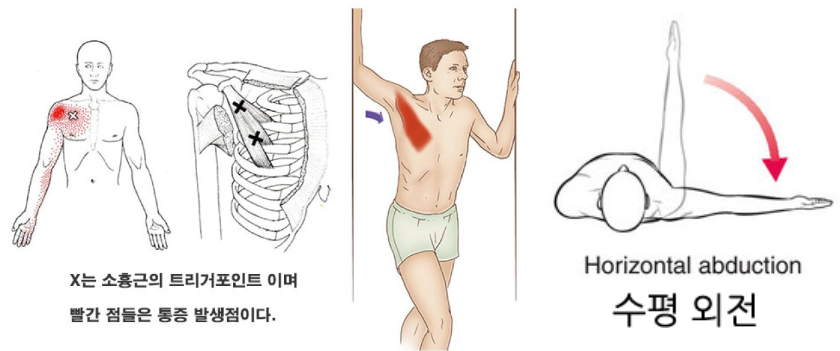

가장 흔한 이유로서 견갑골의 안정화를 도와주는 근육들의 문제가 있을 때 발생됩니다. 이러한 역할을 도와주는 근육들은 상부승모근, 전거근, 하부승모근, 능형근, 견갑거근, 소흉근이 작용해줍니다.

특히 오훼돌기(Coracoid process)에 붙는 소흉근(Pectoralis minor), 이두근건 장두(Short head Of biceps)의 단축은 견갑골을 위에서 아래로, 앞으로 잡아당기게 되면서 견갑골의 앞쪽 기울임(Anterior tilt)을 유발하며 문제를 일으킬 수 있습니다. 따라서 충격파 치료 시 치료포인트가 이두근의 원위부인 팔꿈치 오목 상부인 이유가 됩니다.

소흉근, 이두근 단두의 단축 -> 앞쪽기울임(Anterior tilting) 상태가 유지 -> 충돌 증가

반면 어깨 뒤쪽은 상대적으로 관절와와 상완골두가 좁아지며 외회전, 수평외전 시 극상근, 극하근이 관절와순과 충돌이 많아지며 내적충돌을 일으킬 수 있습니다.(Internal impingement) 이 때 내적충돌은 전상방, 후상방에서 각각 일어날 수 있고, 주로 후상방에서 나타납니다.

참고로 내적충돌증후군은 어깨후방의 관절낭의 구축에 의해서 발생되며, 야구에서 투수가 공을 반복적으로 던지면서 생길 수 있습니다.